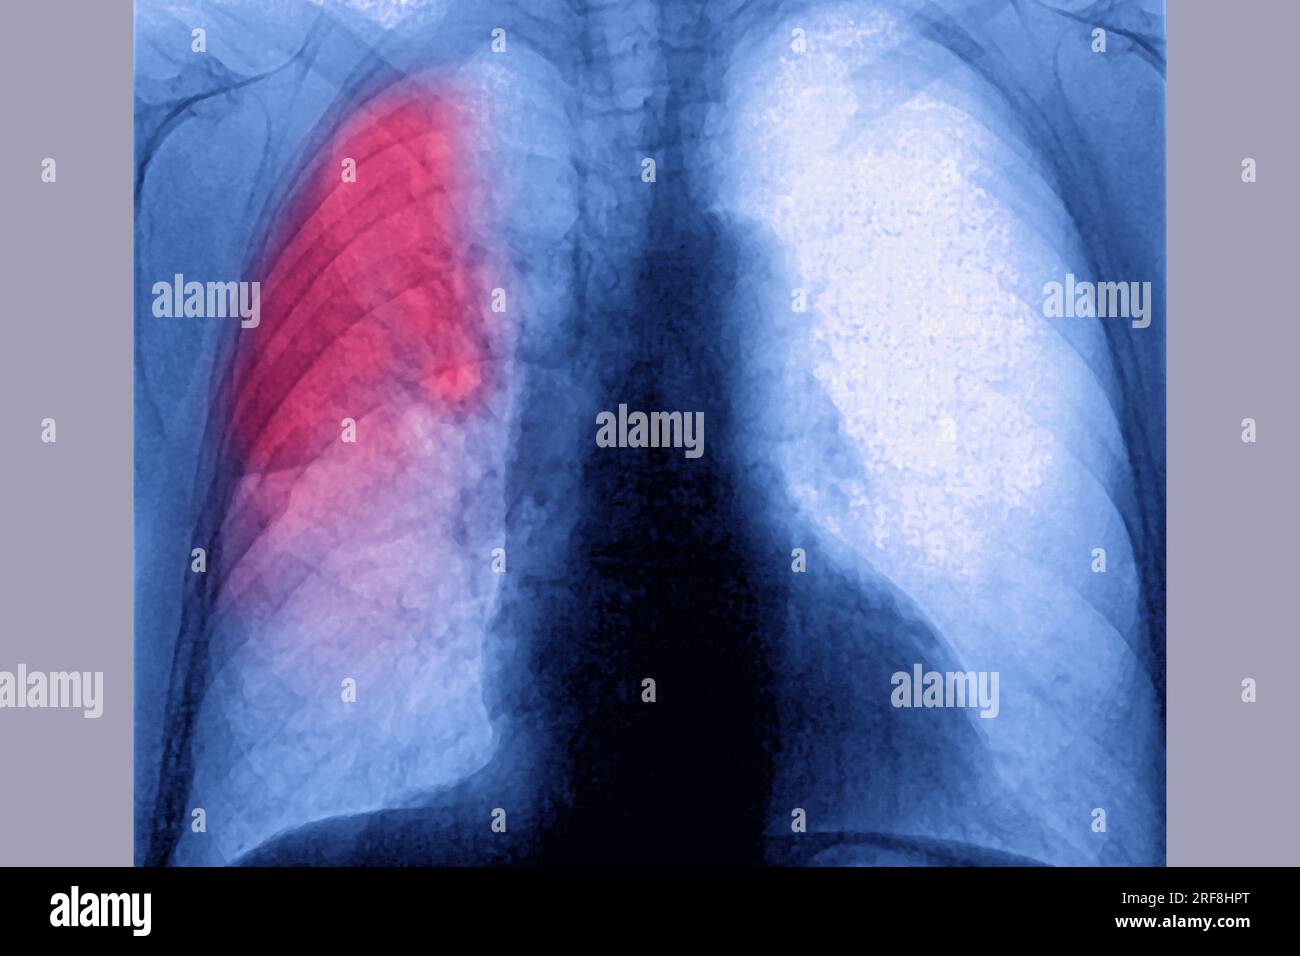

RM2RF8HPX–Pneumonie du poumon droit (infection respiratoire aiguë) révélée par une radiographie thoracique frontale.

RM2RF8HR9–Pneumonie du poumon droit (infection respiratoire aiguë) révélée par une radiographie thoracique frontale.

RM2RF8HPN–Pneumonie du poumon droit (infection respiratoire aiguë) révélée par une radiographie thoracique frontale.